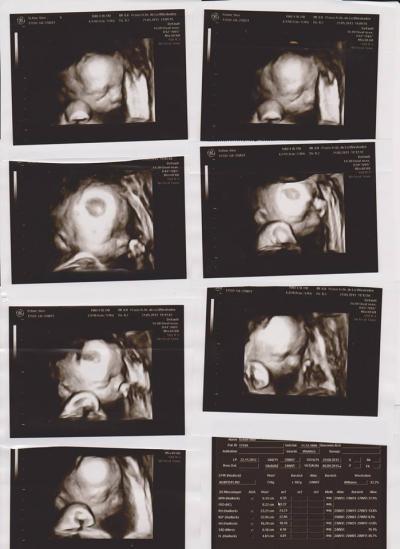

Ich hab das gefühl alles zieht sich wie Kaugummi... Wie war das bei euch ab der 30 ssw? also als dann endlich die 3 davor stand? bis jetzt / heute... ich will irgendwie nicht mehr ... der bauch ist bei allem und überall im weg... dann die baustelle , das schwere atmen bei heißem wetter... freu mich auf meinen stinker..anbei mal 4D bilder von der 26ssw.